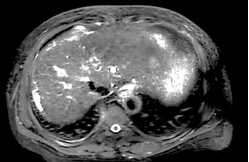

Ø 术前影像学检查

肝 S2 段及肝 S4 段见类圆形 T1WI 低、T2WI-SPAIR/DWI/ADC 高信号,较大者长径

约 10mm,界清。

T2 SPIR 横轴位